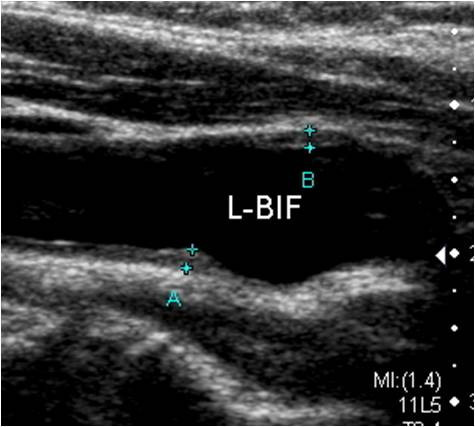

- 플라크 위치와 크기

- 협착률(혈관이 얼마나 좁아졌는지 퍼센트로 표시)

- IMT 수치(혈관 노화 및 동맥경화 지수)